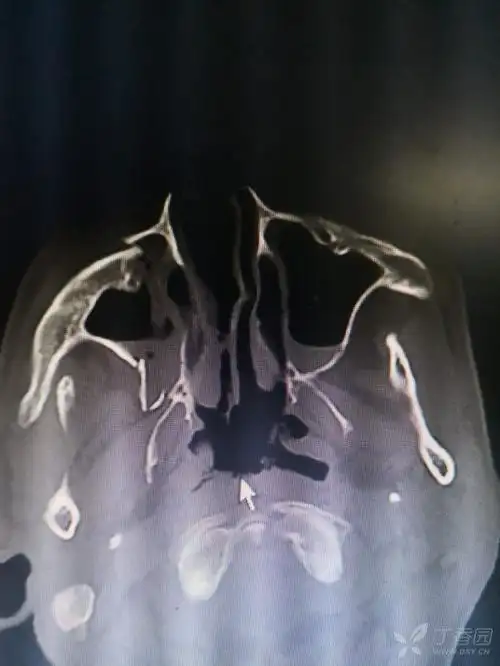

【病例讨论】上颌骨骨折何以引起张口受限 [病例帖]

【急诊】颧骨骨折,上颌骨骨折ct表现

上颌骨骨折

上颌骨骨折 [病例帖]